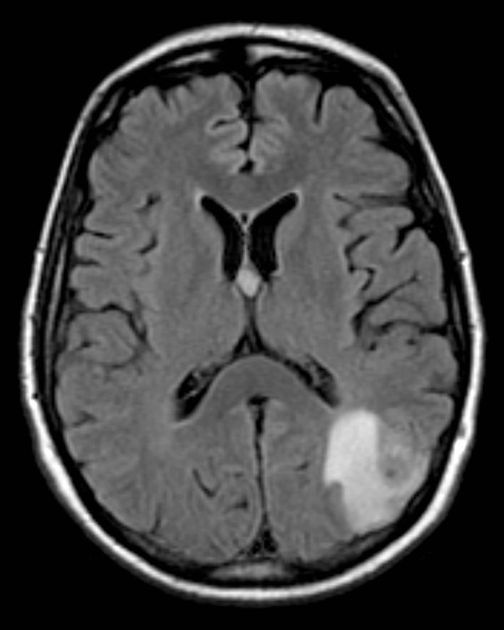

“On initial inspection, there is a suspicious lesion in the left parieto-occipital lobe, but I will proceed to go through it systematically.”

B – Looking at the film, there are no signs of an extra/subdural bleed and no intracranial bleeding.

C – The cisterns are clear and no sing of a subarachnoid haemorrhage.

B – The are no signs of a midline shift. There is a hyperdense area in the left parieto-occipital lobe. It has well defined borders and a ring of oedema around it.

V – The ventricles are not enlarged and there is no signs of an intraventricular bleed.

B – There are no obvious skull fractures.

In summary the key finding is a mass in the left parieto-occipital region.

Diagnosis

Tumour (metastasis)